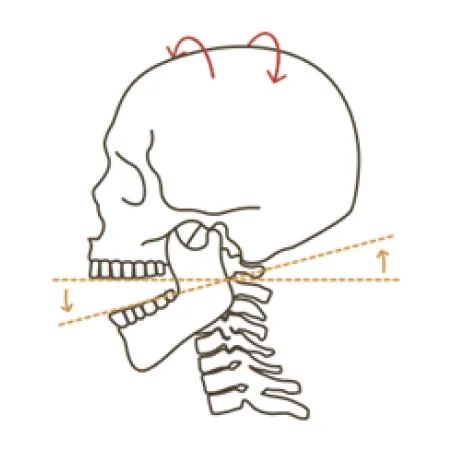

턱관절 교정의 핵심?

두개골과 경추를 함께 교정하는 것!

턱관절은 목뼈 1,2번 및 두개골과 함께 움직이기 때문에 턱관절에 문제가 생기면 목뼈과 두개골은 함께 틀어지게 됩니다.

따라서 턱관절 교정시 추나요법과 두개천골요법을 이용하여 목뼈 1,2번과 후두골, 측두골, 나비뼈를 동시에 교정하는 것이 치료효과를 높이고 재발률을 감소시키므로 한의학 치료가 꼭 필요합니다.

두개골 + 턱관절 + 상부 경추 (목뼈 1, 2번) 교정이 중요합니다.

우리 몸 중 움직임이 가장 많은 턱관절은 상부 경추 (목뼈 1,2번)를 중심축으로 움직입니다.

이 상부 경추가 틀어지면 후두골을 제대로 받치지 못하고, 두개골 또한 점점 틀어져 안면비대칭이 나타나게 됩니다.